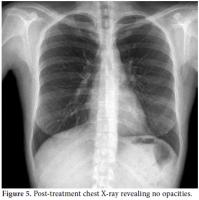

During the clinical follow-up period, the patient's ECG showed dynamic anterior ST-T changes in the precordial derivations (Figure 1), and repeat measurements of these markers revealed a typical course of ACS that featured a relevant rise and fall in TnI. Therefore, the patient underwent coronary angiography which revealed a distally occluded left anterior descending coronary artery (Figure 2). Percutaneous transluminal coronary angioplasty was performed on the occluded site, and because of the thrombotic view of the lesion with a remnant of 30% stenosis accompanied by thrombolysis in myocardial infarction (TIMI) three flow, medical therapy with tirofiban infusion was prescribed for up to a period of 24 hours instead of stent implantation.

Consultations were then held with the pulmonary medicine and rheumatology departments regarding the eosinophilia identified in the CBC, pulmonary opacities revealed via chest X-ray, and the patient's past history of asthma (Figure 3). Furthermore, cranial computed tomography (CT) was performed on the day after the angiography which showed neurological involvement or paranasal sinus abnormality with a prediagnosis of CSS. The results of the cranial CT were also consistent with chronic sinusitis. The presence of asthma, hypereosinophilia of >10%, chronic sinusitis, and pulmonary opacities represent four of the six ACR criteria required for the diagnosis of CCS.[5] Our patient tested negative for anti-nuclear antibodies (ANAs), anti-double stranded DNA (antidsDNA), extractable nuclear antigens (ENAs) and anti-neutrophil cytoplasmic antibodies (ANCAs). The corticosteroid methylprednisolone at an initial dosage of 80 mg per day (1 mg/kg/d) was prescribed after the termination of the tirofiban infusion. Afterwards, the patient's eosinophil levels in the CBC decreased to normal ranges, and symptomatic relief was completely provided. Control coronary angiography was performed one week later, and the thrombotic lesions had disappeared (Figure 4). In addition, chest radiographs showed complete resolution of the opacities (Figure 5). After two more weeks, control echocardiography was performed revealing a normal morphology of the ventricles without any segmental wall motion abnormalities. Furthermore, the pericardial fluid had also disappeared.